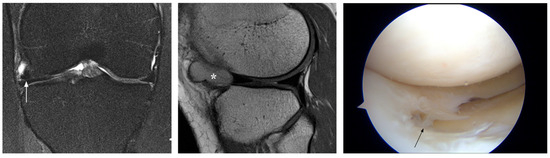

3.3. Equivocal Errors

| 21 | F, 56 y | 5 | grade 2 posterior horn | tear posterior horn | PM | |

| 14 | M, 28 y | 8 | grade 2–3 posterior horn | undersurface tear posterior horn | acute | R |

| 22 | M, 40 y | 74 | grade 2 posterior horn | degenerative tear posterior horn | PM | |

| 23 | M, 48 y | 7 | grade 2–3 posterior horn | large tear posterior horn | acute | PM |

| 24 | M, 31 y | 7 | grade 2 posterior horn | undersurface tear posterior horn | acute | R |